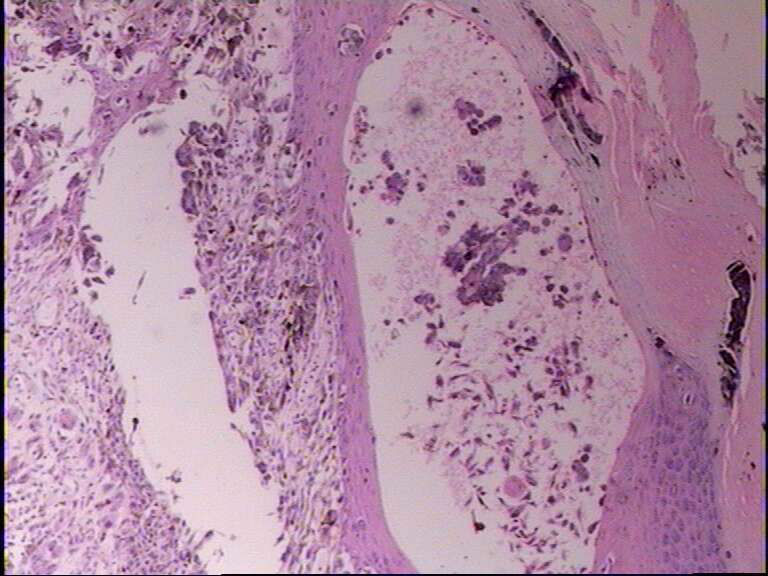

示指末端,指甲下肿物,指甲破坏,黑色面积1*0.7